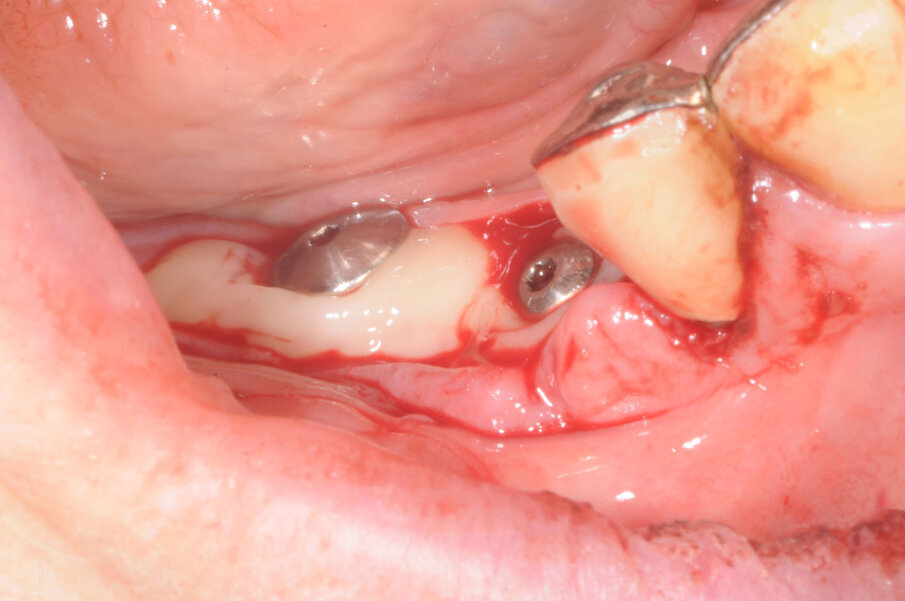

Una paziente di 73 anni lamentava mobilità a una porzione di protesi fissa nel settore 4. All’osservazione clinica e radiografica (Fig. 1), si evidenziava che il pilastro in posizione 45 si era decementato ed era stato completamente distrutto dalla carie. A seguito del sovraccarico il connettore tra i denti 43 e 44 si era fratturato e questo causava mobilità al dente 44 per trauma occlusale. Nonostante il ponte fosse stato realizzato molti anni prima la paziente desiderava mantenere la parte ancora funzionante e sostituire solo i due denti mancanti nel settore 4. Il ponte è stato sezionato tra i denti 44 e 45 e i due denti a sbalzo sono stati rimossi.

Il connettore è stato arrotondato e lucidato e nessun altro intervento è stato eseguito sulla protesi preesistente. All’anamnesi la paziente comunicava di essere in terapia con anticoagulanti a causa di stent coronari applicati circa 5 anni prima. Al momento godeva di buona salute e agli esami clinici e strumentali non si evidenziavano problemi cardiaci. È stata eseguita una dental-scan (Fig. 2), dalla quale si evidenziava che in posizione 46 l’osso residuo al di sopra del canale mandibolare misurava circa 4,5 mm.